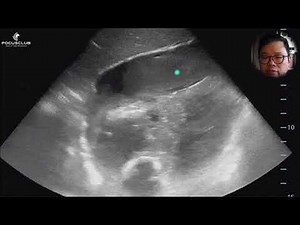

Exam Stroke On a Patietnt - July Update 2025 Anime Last